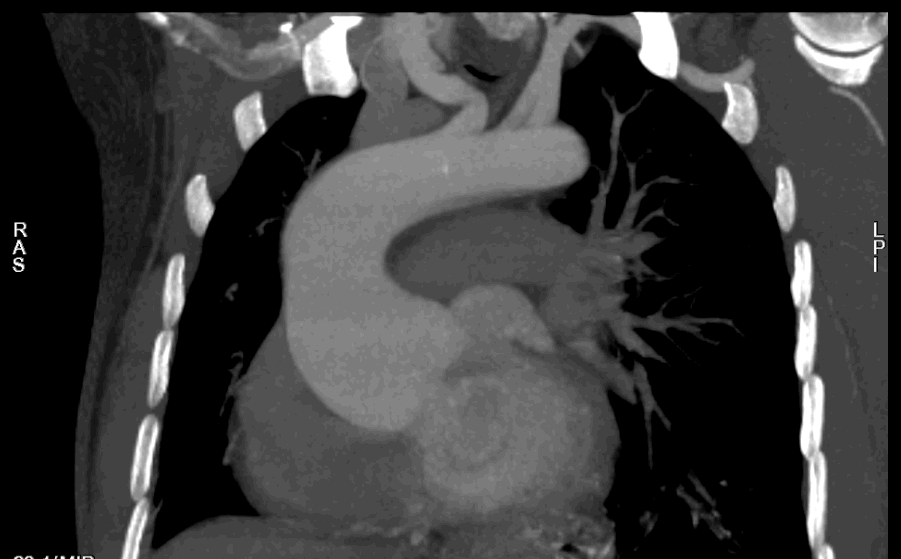

Bentall术前主动脉CTA 例2

为什么叫哈巴狗钳2023学术荟萃|王云:右侧肋间小切口体外循环心脏手术_https://www.jmylbn.com_新闻资讯_第11张

为什么叫哈巴狗钳2023学术荟萃|王云:右侧肋间小切口体外循环心脏手术_https://www.jmylbn.com_新闻资讯_第12张